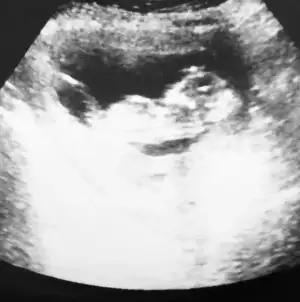

Kız görünüyor kaç haftalık USG 11 12 13 haftalar olmalıMerhabaIkra meyra benim içinde bakar mısınız rica etsem ilk çocuğum olduğu için merak ediyorum :) herkes erkek dedi ama sizinde yorumunuzu çok merak ediyorum

Valla 12+1 o görüntü herkes erkek dedi ama hayırlısı bakalımKız görünüyor kaç haftalık USG 11 12 13 haftalar olmalı![]()

Dikkatli bakar mısınız lütfen sanki bir çıkıntı var gibi pipiye benziyorKız görünüyor kaç haftalık USG 11 12 13 haftalar olmalı![]()

Evet baktım acısı paralel olarak iniyorDikkatli bakar mısınız lütfen sanki bir çıkıntı var gibi pipiye benziyor

Kız görünüyorYani ne demek oluyor peki

Erkek görünüyorbenim usg leri de yorumlayabilir misiniz acaba![]()

Peki kesin midir değişir mi sonradan bu hafta eşime sürpriz yapmayı düşünüyorumdaKız görünüyor![]()

Tahminim kız ama yinede Dr bekleyinPeki kesin midir değişir mi sonradan bu hafta eşime sürpriz yapmayı düşünüyorumda